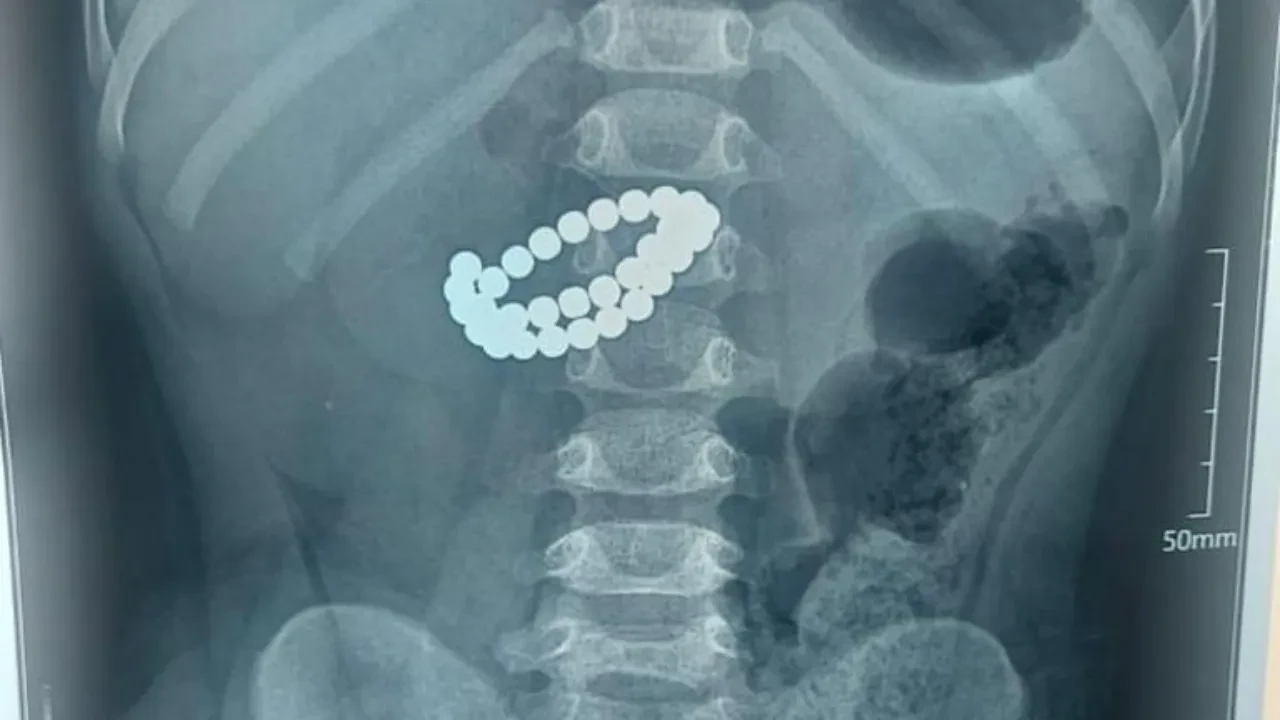

31 магнит оказался в кишечнике полуторагодовалого ребенка в Алматы

В приемное отделение в крайне тяжелом состоянии приняли малыша, которому 1 год 9 месяцев. Ему провели обследование, в ходе которого врачи обнаружили инородные объекты - а именно 31 магнит.

Ребенку сделали хирургическую операцию, ушили множественные перфорации тонкой кишки, провели санацию и дренирование брюшной полости, а также трансанальную интубацию кишечника. В итоге малыша удалось спасти.

Медики призывают родителей исключить доступ детей к магнитным игрушкам, магнитным шарикам и любым предметам, содержащим мелкие магниты, и внимательно следить за безопасностью малышей в быту.